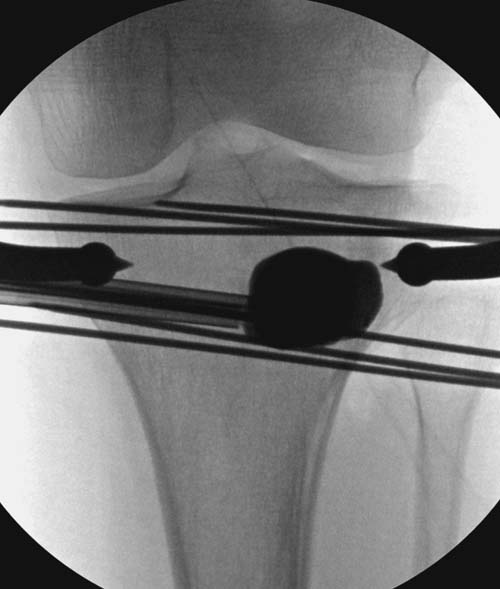

Re: Импрессионный перелом латерального мыщелка левой большеберцевой кости.

Устранение импрессии, костная аутопластика, остеосинтез опорной пластиной

оперировать вероятнее всего надо, импрессия приличная , думаю около 1,5 см, только вот она в задних отделах, преимущественно. Если ставить опорную пластину, то делать это нужно сзади, иначе никакой опорности, а задний котртекс по КТ похоже замят

Учитывая, что у пациента молодой возраст(судя по рентгенограммам,абсолютно показано восстановление суставной линии: подменисковый доступ,подъём импренированной части мыщелка, костная аутопластика, остеосинтез, решение вопроса с мениском (шов либо парциальная резекция)).

Как подсказывают, можно с противоположной стороны приподнять сустав и заполнить костный дефект. Параллельные винты создадут достаточную опору, но иногда buttress plate за счет диафиза создает дополнительную стабильность. Структуральный материал для профилактики от раннего коллапса, и пластическим материалом служит более твердый синтетический материал (Osteoset DBM) или аутокость.

Для лечения некоторых видов центральной импрессии (Schatzker III) можно применить методику Balloon tibioplasty, которая позволяет приподнять сустав без дополнительных доступов. Для информации здесь недавний пример, дефект заполнен жидкой формой композитного материала PRO-DENSE: http://www.wmt.com/prodense/product_overview.asp